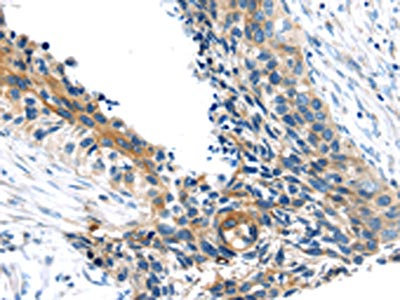

The image on the left is immunohistochemistry of paraffin-embedded Human esophagus cancer tissue using CSB-PA980506(TSC2 Antibody) at dilution 1/20, on the right is treated with synthetic peptide. (Original magnification: ×200)